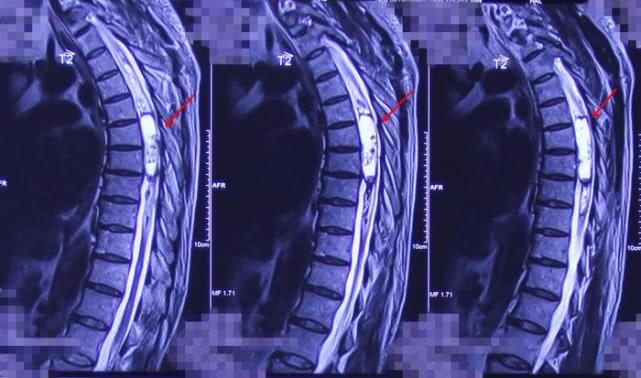

胸5-7

颈椎、胸椎MR平扫和增强显示,颈1-2、胸5-7水平椎管内髓外硬膜下可见,大小分别约为2.5cm*2.1cm*2.6cm、2.0cm*2.0cm*4.5cm的肿瘤物,贾主任最终诊断周叔颈1-2椎管内占位性病变,考虑是脊膜瘤,胸5-7椎管内占位病变,考虑是室管膜瘤。